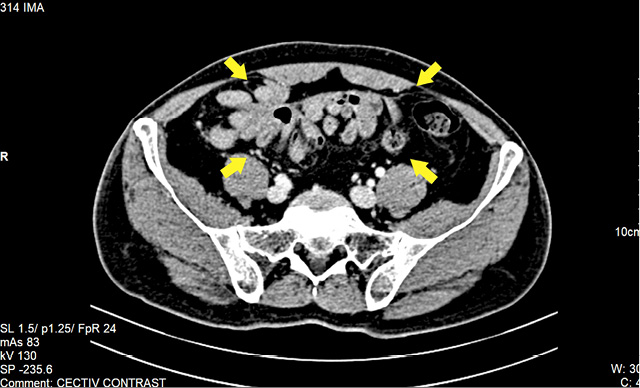

We present a case of a 62-year-old man who presented to the surgical emergency department with complaints of distension of the abdomen and inability to pass stool or gas for 48 hours. He also had three episodes of bilious vomiting. On clinical examination, there was tachycardia and signs of dehydration. The abdomen was distended with absent bowel sounds. He was admitted and started on parenteral intravenous fluid resuscitation. All investigations including hematology and biochemistry were normal. Chest radiograph with both domes of the diaphragm was normal. An abdominal radiograph revealed multiple air-fluid levels suggestive of small bowel obstruction. A contrast-enhanced CT scan of the abdomen revealed dilatation of proximal ileal and jejunal loops with abruptly cut off at the level of the proximal-mid ileal loop. There was circumferential thickening of proximal-mid ileal loops. There was twisting of distal jejunal and proximal ileal loops along with a defect in the mesentery at the level of umbilicus likely to be a small bowel trans mesenteric internal hernia (Figures 1, 2). Abdominal Tuberculosis workup was done with Polymerase Chain Reaction (PCR) for mycobacterium, manteaux test and Cartridge Based Nucleic Acid Amplification Test (CB-NAAT) Sputum were negative. He was managed conservatively with nasogastric decompression with a nasogastric tube, intravenous fluids, and symptomatic drugs. There was partial relief of obstruction after the second day of admission.

Clinical diagnosis is difficult because of non-specific symptoms. Plain radiographs of the abdomen may reveal nonspecific bowel loop dilatation and air-fluid levels. Ultrasound abdomen may reveal a cauliflower or a trilaminar appearance of the bowel. CT has facilitated accurate preoperative diagnosis, long before the patient presents with full-fledged symptoms of acute intestinal obstruction. CT scan is the imaging of choice and plays a significant role in excluding the secondary causes and helps in patient management. The identification of thickened contrast-enhanced peritoneal membrane with encapsulated bowel loops called “cauliflower sign” is a significant finding. CT also helps in identifying the cause and delineating the complications [4–6].